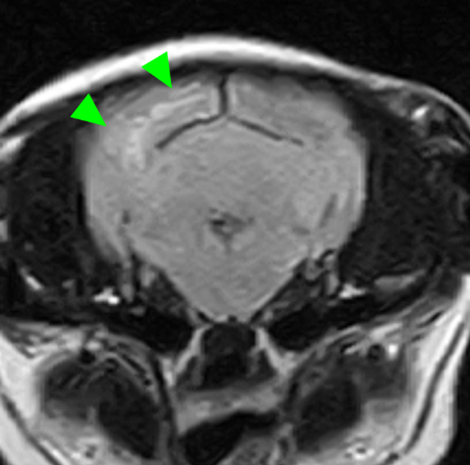

本症例のMRI検査所見:

・前頭葉白質領域(右>左)および右側大脳白質領域(側頭葉・後頭葉)にT2強調画像/FLAIR画像で高信号を示し、一部造影増強を示すびまん性の所見を認める。この所見は、DWI画像で高信号を示し、ADC-mapで大半は等~低信号を示す。

・透明中隔は欠損を疑うが、顕著な側脳室拡大を疑う所見は認められず、脳溝も明瞭である。